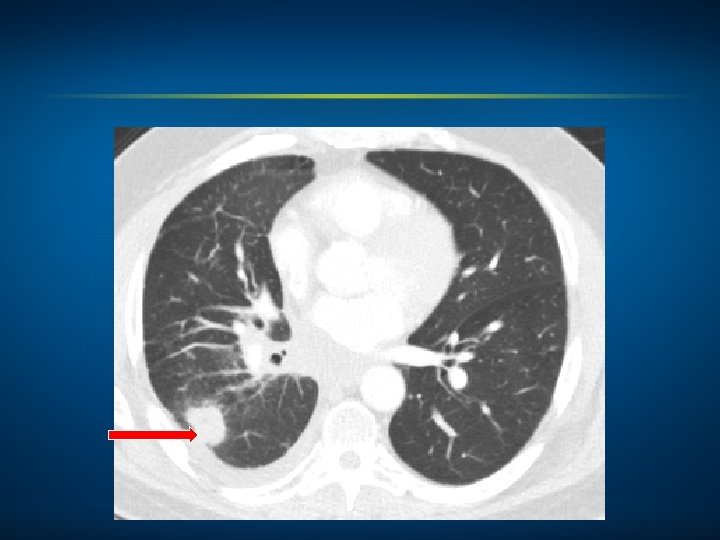

Oncology Treatment Timeline Case 4: A 52 -Year-Old Woman with Cancer of Unknown Primary and ALK-Rearranged Metastases (Ms Goodwin) WBRT Dec 2005 Carboplatin, paclitaxel and canfosfamide on clinical trial Crizotinib WBRT March 2006 April 2010 Feb 2014 Alectinib on clinical trial March 2014

4/19/2014 6/07/2014